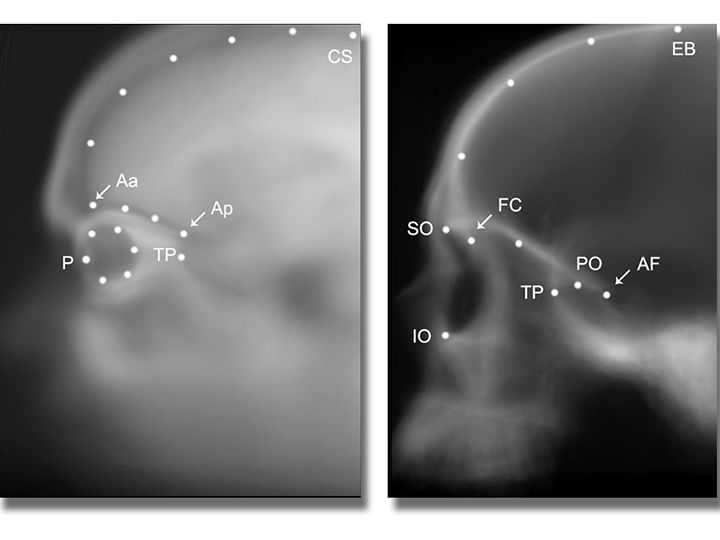

Sofía Pereira Pedro y Emiliano Bruner, miembros del Grupo de Paleoneurobiología del Centro Nacional de Investigación sobre la Evolución Humana (CENIEH), acaban de publicar en la revista Journal of Anatomy un estudio de morfometría sobre la relación espacial entre ojos y cerebro en humanos modernos, fósiles, y chimpancés. La investigación ha analizado tejidos blandos (ojos y cerebros), mediante resonancia magnética, y tejidos duros (órbitas y cavidad craneal), a través de tomografía computerizada.

“Nuestros ojos y órbitas se encuentran debajo de los lóbulos frontales del cerebro, mientras que los chimpancés los tienen en una posición anterior, delante de los lóbulos frontales. En los homínidos fósiles se observa una situación intermedia”, afirma Emiliano Bruner. Los factores principales que determinan las diferencias entre individuos adultos son la distancia entre ojos y lóbulos temporales del cerebro y la orientación de las órbitas. En función de estas variaciones, los individuos pueden ser más o menos susceptibles de sufrir una deformación del globo ocular, causada por límites espaciales.